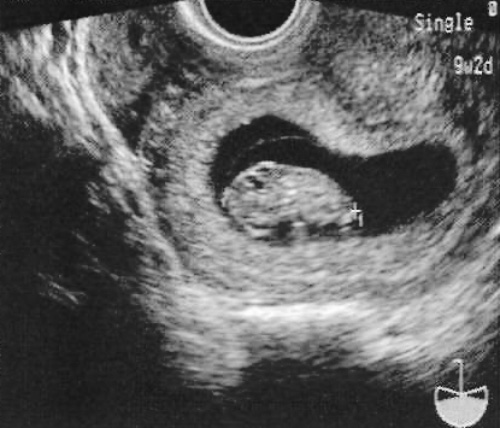

До 8 недели предполагаемого гестационного возраста КТР (копчико-теменной размер) и шейно-копчиковое расстояние практически отражают размер эмбрионального диска (6-я неделя). Точность измерения КТР в период от 3-5 дней до 11-й недели беременности включительно составляет примерно 8% (фото 12).

Фото 12. Копчико-теменной размер (срок беременности – 9 недель и 2 дня)